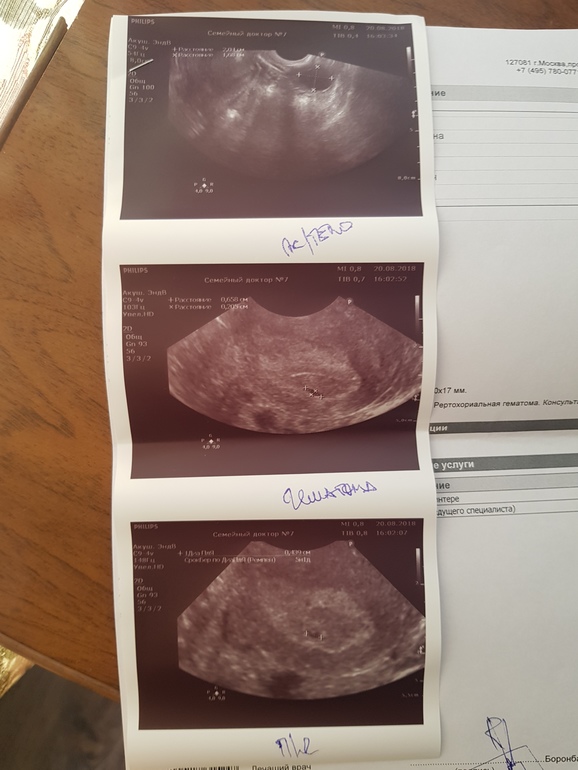

Вопросы про УЗИ, обследования и анализы: что, где, как, когда?Ой, девчули, сделала я сегодня платное узи. Сказали, что срок 5 недель и 1 день, есть плодное яйцо и желточный мешочек, так же маленькая гематома, сказали свечки и ношпу. Но самый главное, не видно эмбриона, очень переживаю😭😭😭